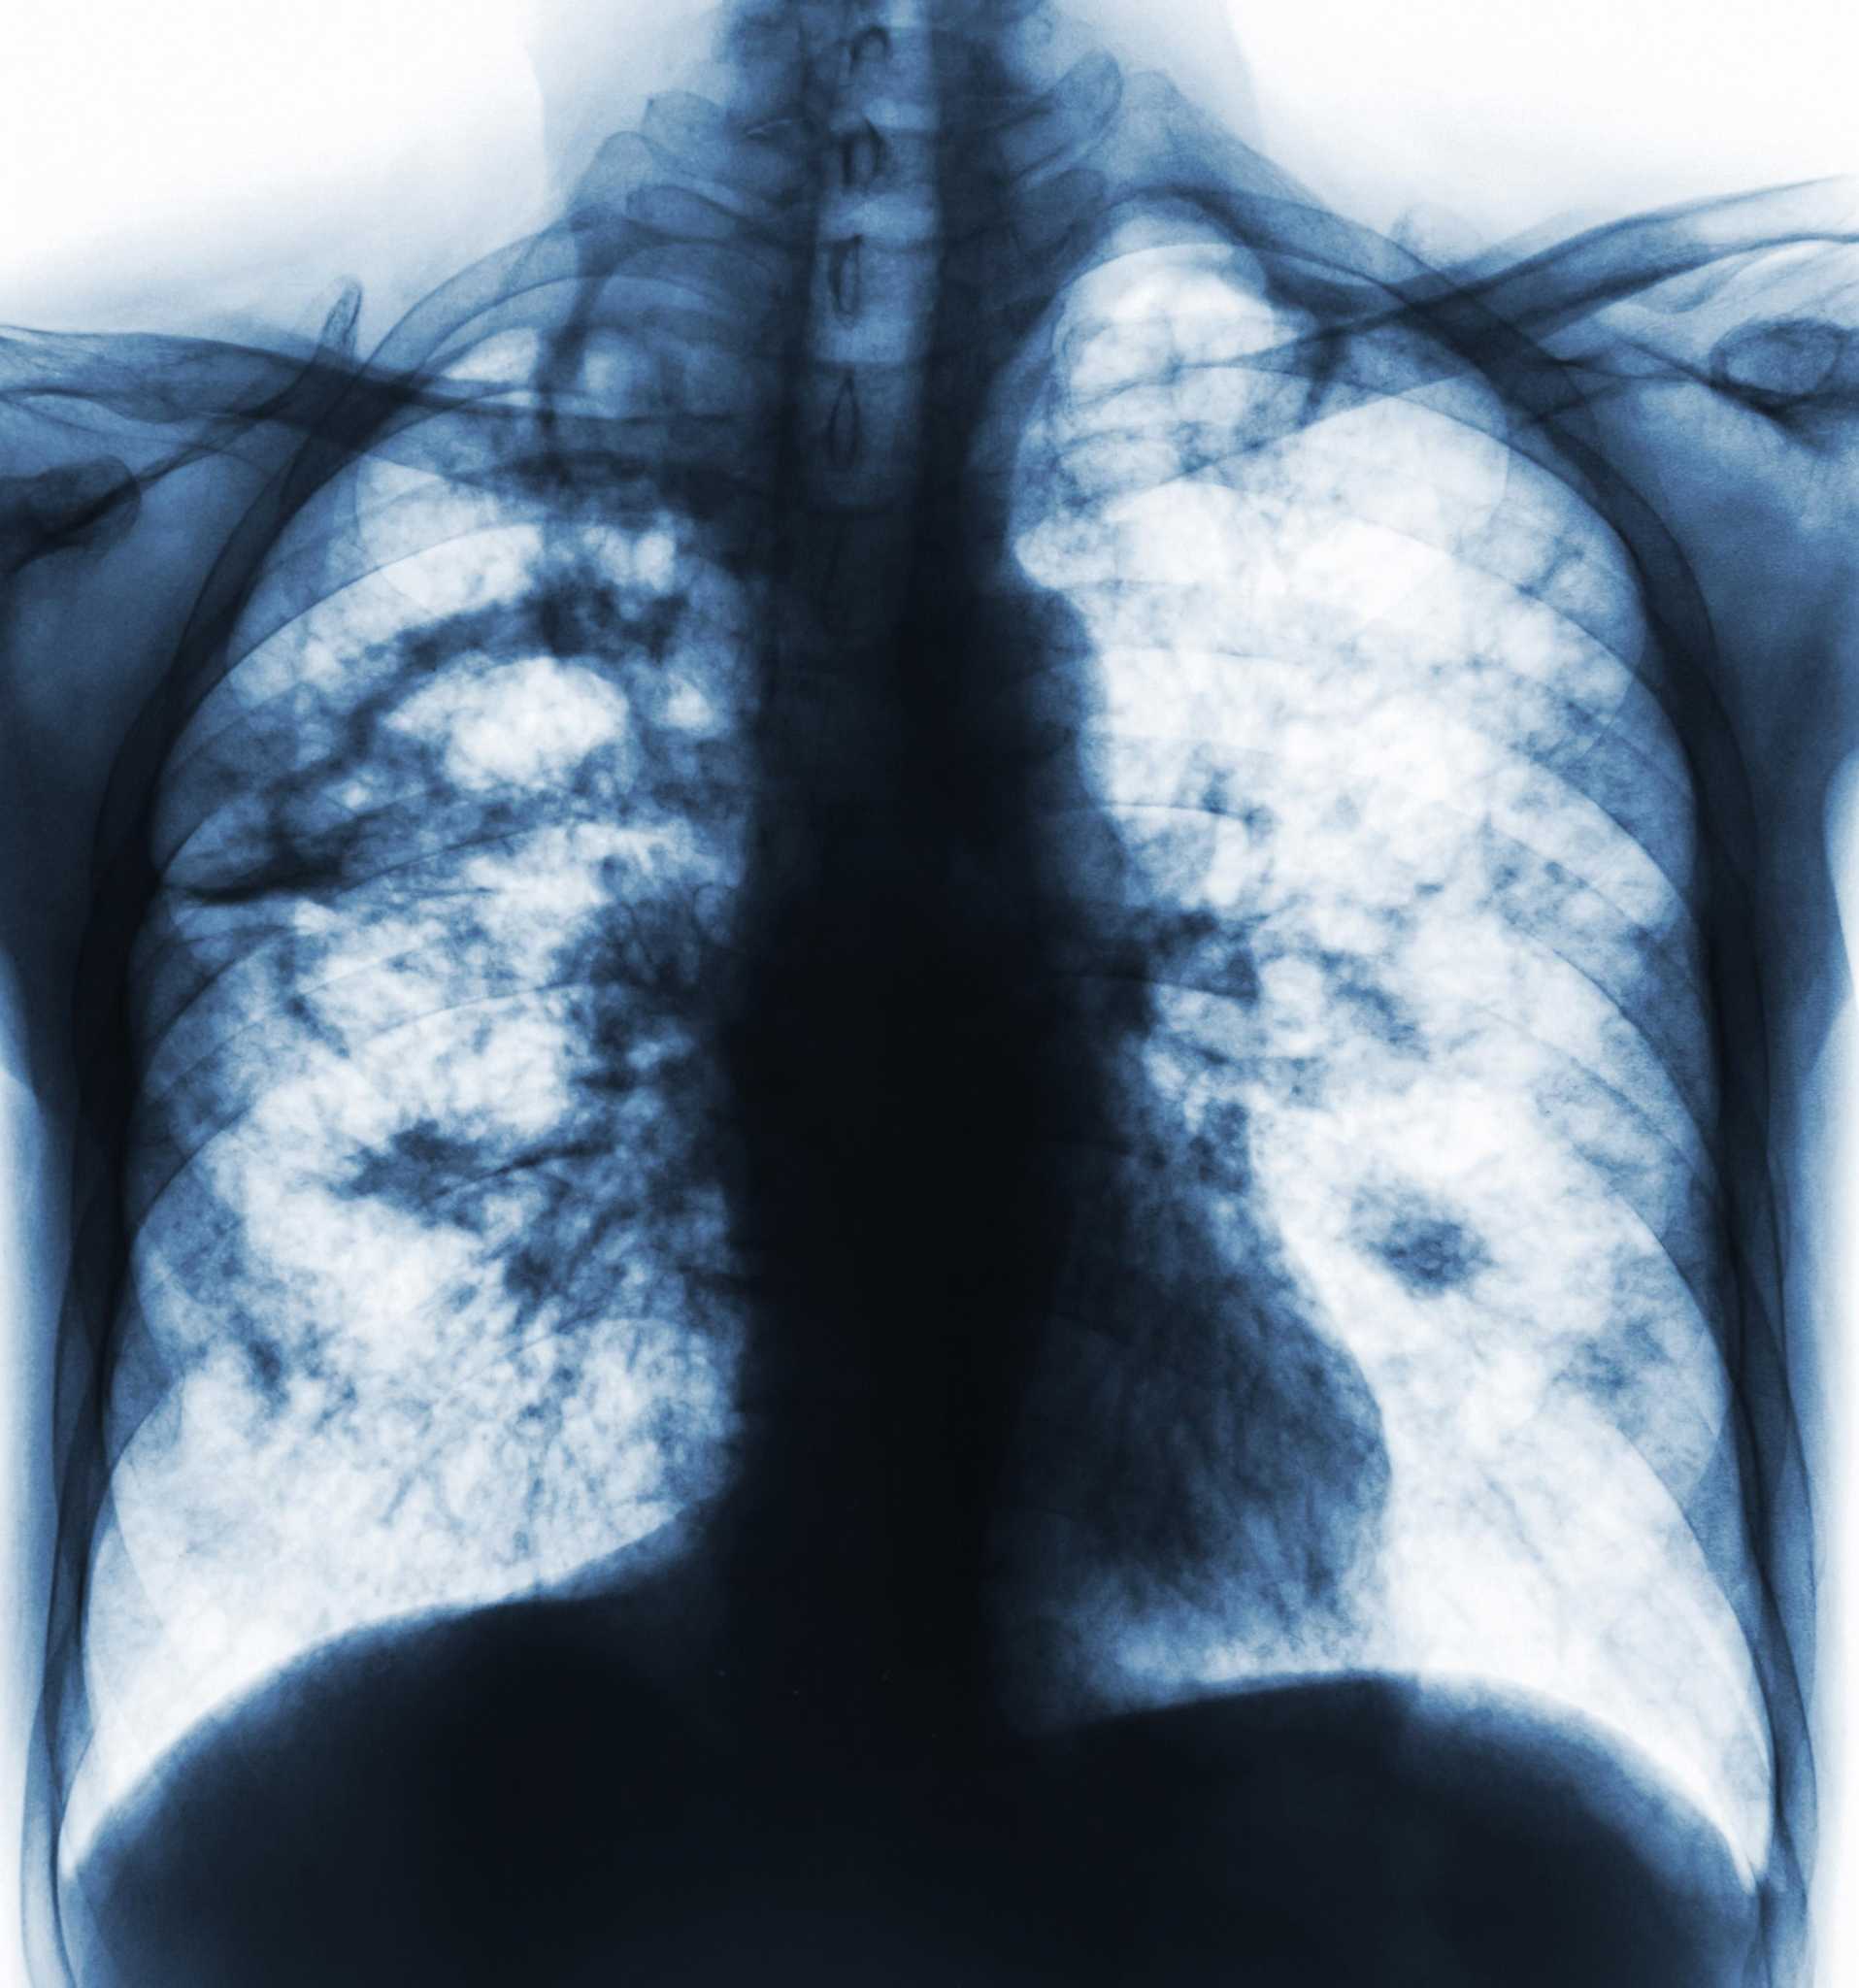

Милиарный туберкулез рентген

Диссеминированный туберкулез рентген

Милиарный туберкулез рентген

Милиарный туберкулез рентген

Острый диссеминированный туберкулёз лёгких рентген

Милиарный туберкулез рентген

Диссеминированный туберкулёз лёгких рентген

Милиарный диссеминированный туберкулез